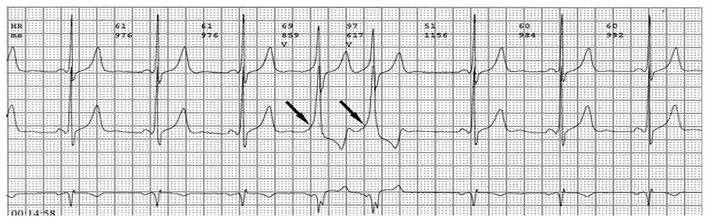

心电图检查及其特征

各旁路引起预激的心电图特征如下:

1、房室旁道

(1)PR间期(实质上是P-δ间期)缩短至0.12秒以下,大多为0.10秒;

(2)QRS时限延长达0.11秒以上;

(3)QRS波群起始部粗钝,与其余部分形成顿挫,即所谓预激;

(4)继发性ST-T波改变。

上述心电图改变尚有分为A、B两型的。A型的预激波和QRS波群在V1导联均向上,而B型V1导联的预激波和QRS波群的主波则均向下;前者提示左室或右室后底部心肌预激,而后者提示右室前侧壁心肌预肌。这种分类方法虽然受到预激是不同部位旁路所致的多变QRS波群的限制,但有助于区别旁路的心室端在左或右、前或后,因而沿用至今。

2、房结、房希旁道

PR间期少于0.12秒,大多在0.10秒;QRS波群正常,无预激波。这种心电图表现又称为短PR、正常QRS综合征或L、G、L(Lown-Ganong-Levine)综合征。

3、结室、束室连接

PR间期正常,QRS波群增宽,有预激波。预激综合征室上性心动过速发作时,预激表现大多消失,心电图表现为QRS波群形态正常的室上性心动过速。并发房扑或房颤时,QRS保持预激特征的不少见,心电图表现为QRS波群畸形宽大的房扑或房颤;心室率大多超过200次/分,甚至可达300次/分。房扑时可呈1:1房室传导,并可能辨认房扑波。房颤时心室律不规则,长间歇之后可见到个别QRS波群形态正常(可能为旁路不应期延长,房室结内隐匿传导作用消失后,冲动全部或大部经房室结传导所致),并可能辨认房颤波。心室率极快时,还可伴有频率依赖性心室内传导改变。

预激综合征的诊断

预激是一种较少见的心律失常,诊断主要靠心电图。

1、典型预激综合征

(1)P-R间期<0.12秒,P波正常;

(2)QRS时间>0.11秒;

(3)QRS波群起始部分变粗钝,称为预激波或δ波;

(4)继发性ST-TT改变。临床上又分为两型:A型预激:预激波和QRS波群在V1导联向上,其旁道位于左侧房室瓣环周围。B型预激:预激波和QRS波群的主波V1导联向下,在左胸导联V5向上,其旁道位于右侧房室瓣环的周围。

2、变异型预激

(1)LGL型综合征 P-R间期≤0.11秒;QRS波群时间正常;没有δ波。

(2)Mahaim型预激 P-R间期≥0.12秒;QRS综合波起始波有δ波,但δ波小;QRS时间≥0.12秒,但增宽轻微。

除上述心电图特征外,心电向量图可作为诊断依据,其特征是各个面上QRS环起始部分运行缓慢成一直线,持续可达0.08秒,以后突然转向并以正常速度继续运行。QRS环运行时间可超过0.12秒。希氏束电图和体表或心内膜标测有助于鉴别各项顶激和进行旁路的定位,在确诊旁道是否参与心动过速折返环方面起重要作用。